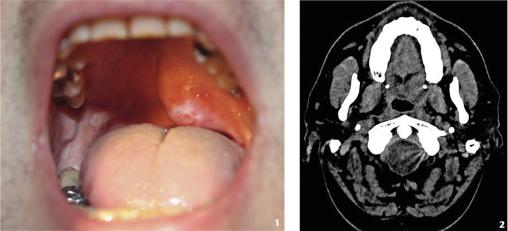

1) Importante voussure de la partie gauche du voile du palais, ulcérée à son sommet. Cette tuméfaction apparue progressivement ne disparaît pas avec l’antibiothérapie et les soins de bouche.2) Le scanner ne montre pas de diffusion métastatique.